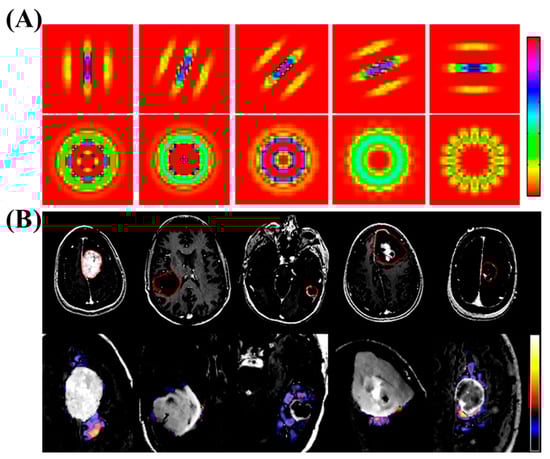

Similarly, ML has successfully been used in diagnosing brain tumors. Zacharki et al. used the textures and sizes of the tumors in MRI images to diagnose whether it is a primary glioma or metastases. This study subsequently grades the glioma by using a pattern classification method. The proposed plan involves a series of steps, such as identifying the area of interest, extracting features, selecting relevant features, and classifying the brain tumors. The extracted features will include the shape and intensity characteristics of the tumor, along with texture features that are rotation invariant. To narrow down the features, a support vector machine with recursive feature elimination will be used. The approach was tested on a group of 102 brain tumors that were diagnosed with different types of cancer, including glioblastoma, meningiomas, and metastasis. Using the binary support vector machine classification method with leave-one-out cross-validation, they achieved an accuracy of 85% in distinguishing metastasis from gliomas, and 88% accuracy in discriminating high-grade tumors from low-grade tumors. The sensitivity for differentiating metastasis was 87%, and the specificity was 79%. The sensitivity and specificity for distinguishing high-grade tumors from low-grade tumors were 85% and 96%, respectively (Figure 7) [55].

Figure 7. (A) The figure displays examples of filters utilized for extracting texture features. The first row demonstrates Gabor filters with the same frequency but different orientations, while the second row showcases rotation-invariant filters. (B) MR images of various brain tumor types are shown, along with an example of texture images extracted from the edematous area. The tumors depicted include meningioma, glioma grade II, grade III, grade IV, and metastasis. In the first row, the tumoral region of interest is displayed using the T1ce image. In the second row, a zoomed-in FLAIR image of the tumor region is overlaid with one of the textural patterns (λ = 8). It is important to note that the presented pattern, shown as a voxelwise texture, is for illustrative purposes and does not reflect our actual calculations. The average texture values, calculated prior to the fast Fourier transform, are also indicated. Copyright (2009) with permission from Wiley [55].